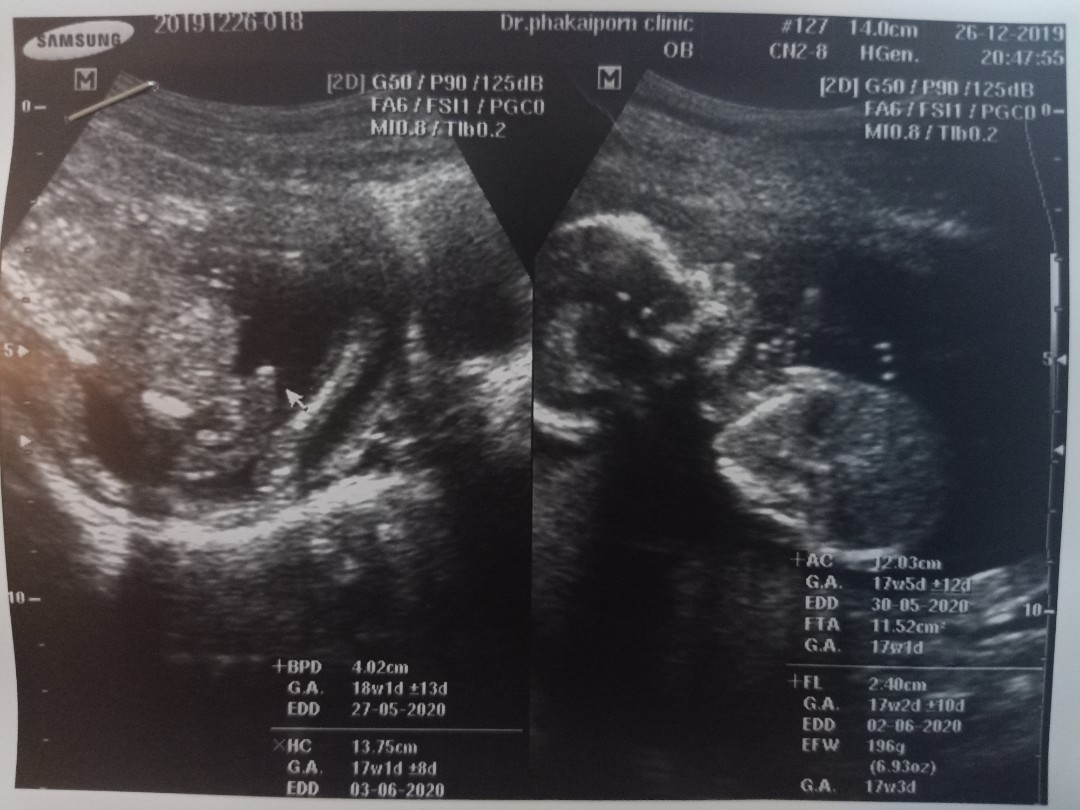

20w2d

วันนี้ไปตามหมอนัดมาค่ะ ได้รู้เพศลูกแล้ว ดีใจมากค่ะ คลอด พค.ค่ะ บ้านไหนได้ลูกผู้ชายบ้างคะ ?❣️